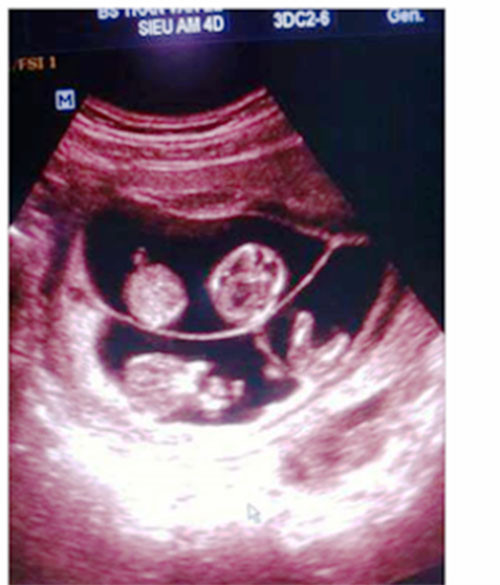

| Hình ảnh mang thai bốn được bác sĩ siêu âm cho chị Xuân chia sẻ trên Facebook. |